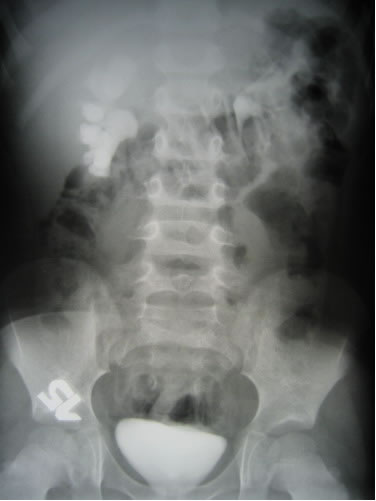

Обзорная и экскреторная урография

УЗИ - Правая почка – 7,8х3,4 см, т.п.

1,0 – 1,1 см. В лоханке определяется конкремент размером

до 2,1 см. В нижней чашечке конкремент размером 0,9 см.

Верхняя чашечка расширена до 1,6 – 1,7 см. Лоханка, средняя

и нижняя группа чашечек не расширены. Левая почка – 6,9х3,4

см, т.п. 1,2 см. ЧЛС не расширена. Конкрементов, объемных

образований не выявлено. Мочевой пузырь внутренний контур

четкий. Толщина стенок 0,2-0,3 см. Конкрементов, объемных

образований не выявлено. Гипертрофии паращитовидных желез

нет.